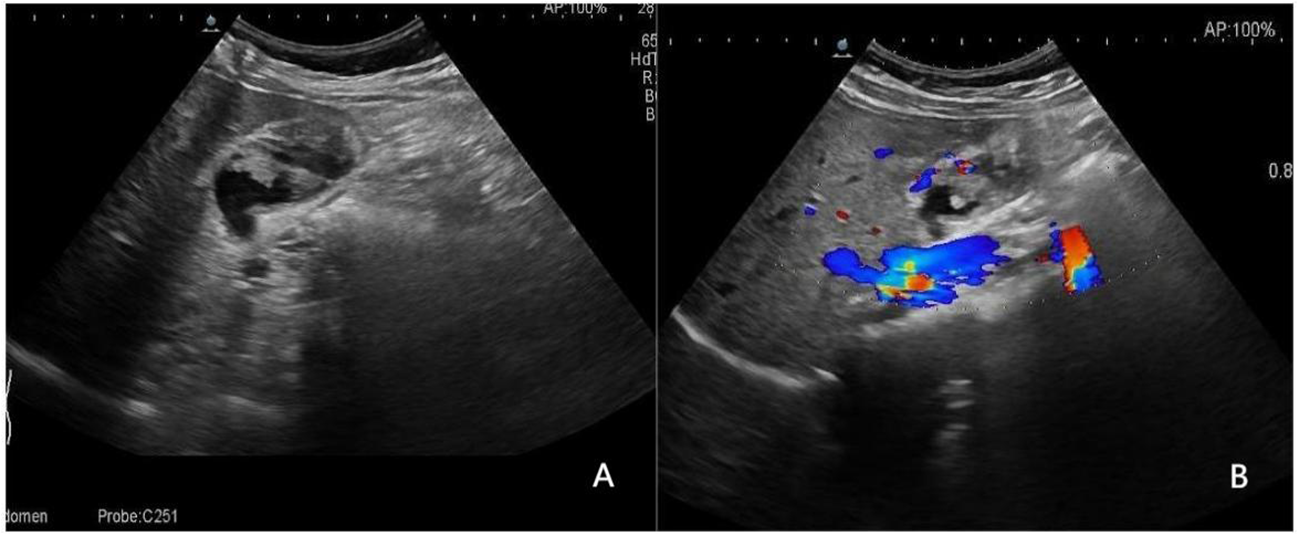

Figure 3

www.frontiersin.org

Figure 3 A 36-year-old woman with pathologically proven xanthogranulomatous cholecystitis. (A) Focak thickening of the base of the gallbladder with layering; (B) CDFI=0.Based on a consensus review of the sonographic findings, the lesion was categorized as GB-RADS 2, GB-RADS+CDFI 2.